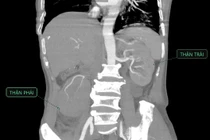

Sỏi niệu quản nếu không được phát hiện và điều trị sớm có thể gây biến chứng như nhiễm trùng thận, ứ mủ đài bể thận, thậm chí nhiễm khuẩn huyết.